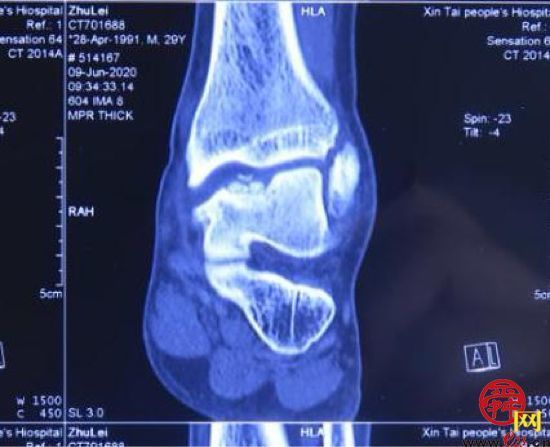

患者,男,28岁,左踝关节疼痛1年,加重3个月,影像学表现为左距骨内髁坏死、塌陷,面积约3*2cm大小。距骨坏死的治疗,对直径在2cm以内的距骨坏死,可以采用自体股骨髁骨软骨移植、自体带骨膜髂骨移植等方法,但对于直径超过2cm的距骨坏死,尤其是年轻患者,一直是治疗的难点。搜索国内外文献,对于超过2cm距骨坏死,一般采用踝关节融合、踝关节置换、同种异体距骨移植、全距骨置换等方法。但上述方法均有弊端:采用关节融合,患者丧失踝关节功能;踝关节置换、全距骨置换对于年轻、距骨单髁坏死患者,创伤大,且需要多次的返修手术;国外有采用同种异体新鲜距骨移植的报道,但目前国内还没有相关的骨组织工程库。经手术团队术前充分讨论,认为3D打印技术因其个性化的设计已经越来越多地应用于临床,决定对患者行3D打印距骨部分置换手术。

(术前患者的影像情况)

手术在朱磊教授的指导下,由许庆家教授主刀,崔宜栋主治医师及刘奔医师作为助手实施完成。术中按照术前设计,将坏死距骨切除,置入设计好的3D打印的距骨半髁假体。术后指导患者早期功能锻炼,术后7天患者顺利出院。